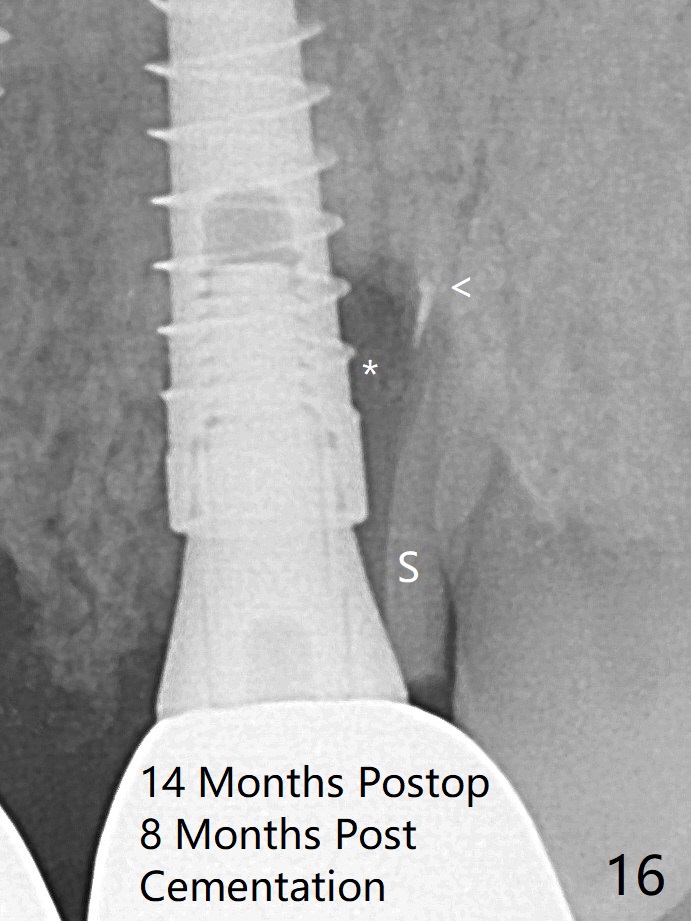

It appears that the socket shield (Fig.16 S) causes infection and loss of bone graft (*).  With periosteal relief and placement of sticky bone (Fig.7 *), PRF and 6-month membrane, the wound is closed with 4-0 PTFE suture (Fig.5).